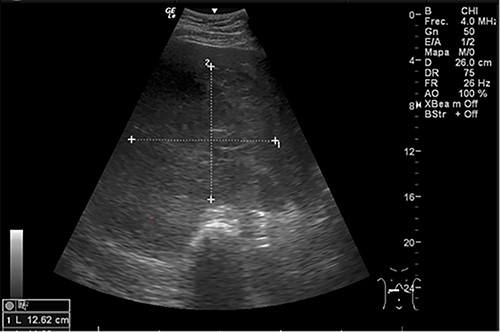

Examination revealed tachycardia, tachypnea, jaundice, dehydration, jugular vein distension, right lung hypoventilation, ascites, upper abdominal tenderness and bilateral lower limb edema. Laboratory workup highlighted neutrophilic leukocytosis, with WBCs exceeding 20 000/μl, along with an abnormal hepatic function panel. The latter showed hypertransaminasemia with ALT predominance over AST (344.7 U/L and 288.5 U/L, respectively), hyperbilirubinemia (10.01 μmol/L) and elevated values of ALP (909.1 U/L) and DHL (709.9 U/L). Of relevance, creatinine elevation (2.11 mg/dl), thrombocytosis (629 × 109/L) and positive D-Dimer (5780 ng/ml) were also noted, so acute kidney injury management and thromboprophylactic measures were initiated. A chest X-ray (CXR) showed a massive right pleural effusion (Fig. 1) and an abdominal ultrasound (US) revealed hepatomegaly with a right nodule (Fig. 2). After further evaluation, tomographic evidence of a right pleural effusion occupying 100% of the lung (Fig. 3) and a 20 cm hypodense, nodular lesion in the right liver (Fig. 4) were identified. These findings were suggestive of an ALA concomitant with an empyema. The patient was admitted into the intensive care unit and prepared for surgery.

Abdominal US at admission: nodular lesion in the right liver lobe.